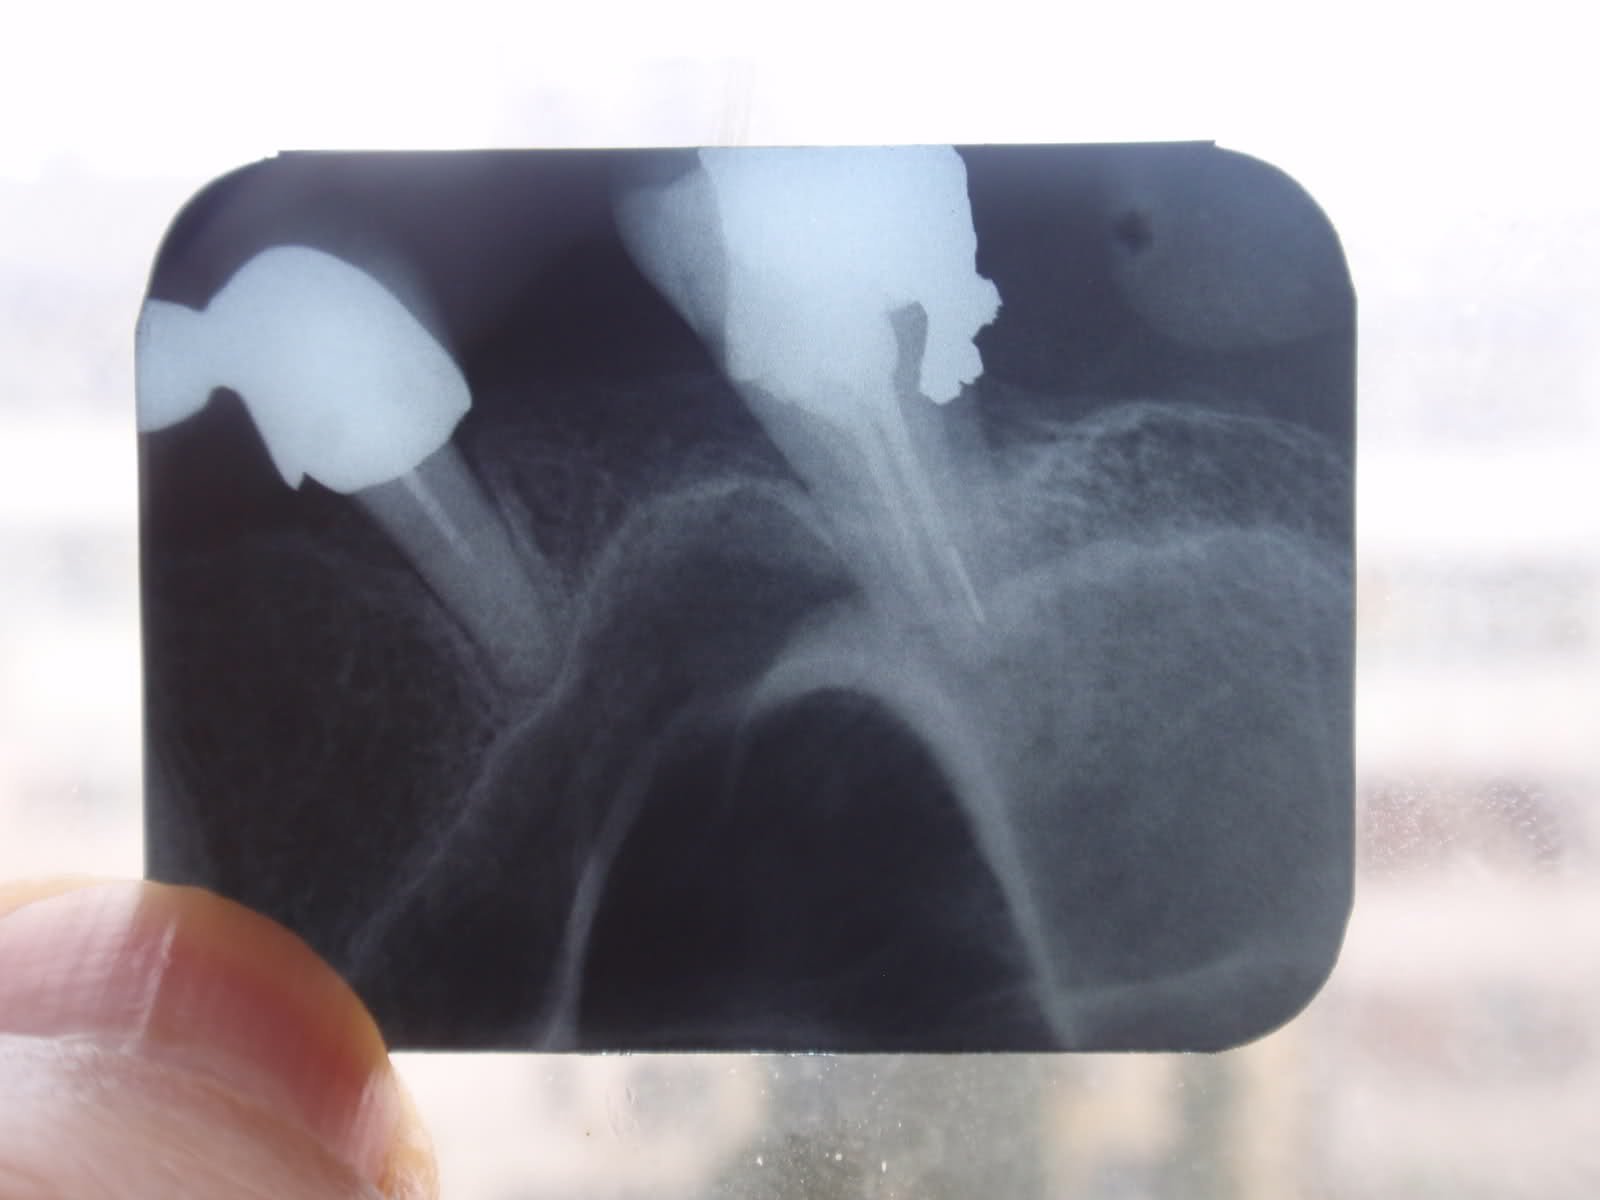

Отново търся мнението на зъболекарите във форума за моята гробница, наречена уста. Тъй като моя зъболекар каза, че като свършим горната част, тогава ще почнем долната. Но съм крайно нетърпелива. По реакцията му разбрах, че и тук има някакъв проблем. Това място е - мое дясно, долу - последен и предпоследен. Толкова усилия съм хвърлила в миналото - за да запазя и лекувам зъбите си, а се оказват пак проблем. Вече ми идва да ги извадя всичките и реша въпроса по Сталински - Няма зъби, няма проблеми! А и защо има такова голямо разстояние между двата зъба, не чувствам такова, а по-скоро тъпа болка - търпима при дъвчене и само ако си събера двете челюсти, ама после минава.

Абе усъмних се и аз. На снимката ми се виждат горни зъби първо, а и между тези двата по мое мнение има изваден зъб.

По показаната снимка съдя че има доста резорбция.Зъбите вече са извадени но това ме навява на мисълта ,че положението във фронта не е по различно или е малко по -добро.

По описние на пациентката горе в ляво има до 23 зъб,като има и липсващи във фронта.Няма как да се пуснат зъби назад.Не и до 26 зъб за да се възстанови дъвкателен център.В дясно зъбите са до 14 -там да кажем че има някаква вероятност.Ще трябва много добре да се прецени пародонта колко може да издържи,как пада натоварването ,има ли аномалии в захапката и ред други неща.